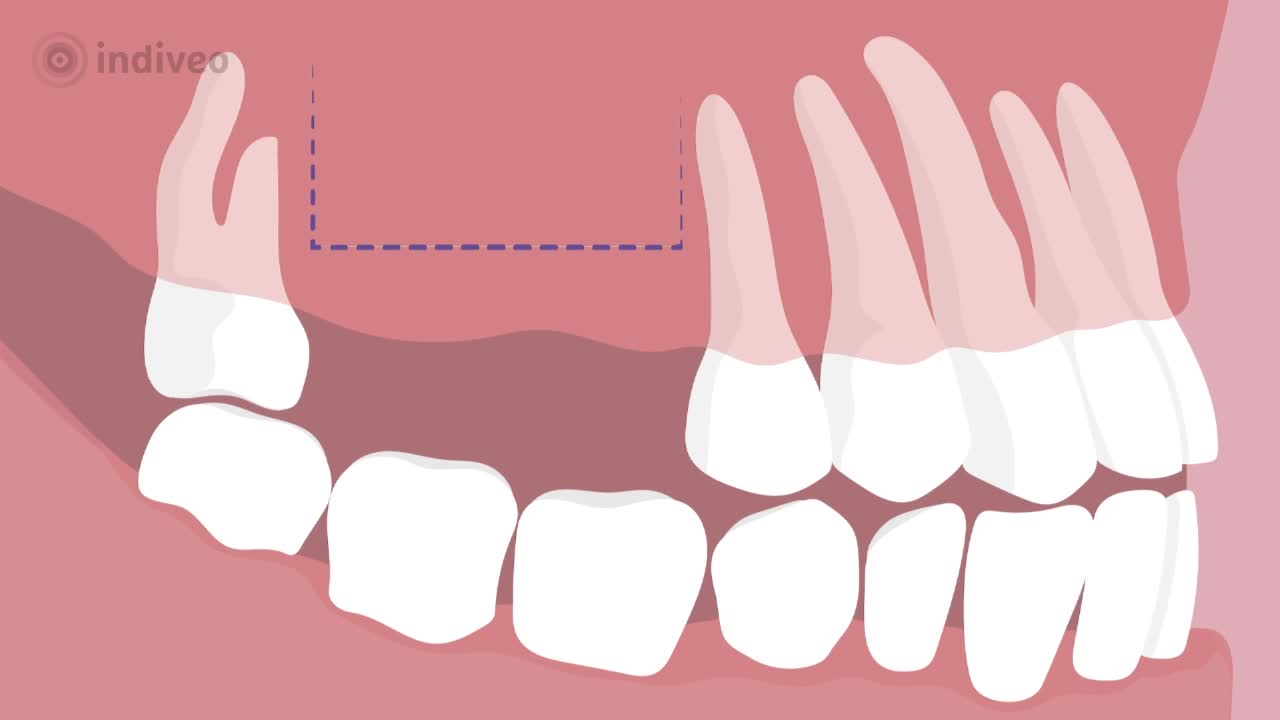

In deze Divi krijgt de patiënt uitleg over een sinusliftoperatie. De patiënt leert waarom er te weinig bot in de bovenkaak is voor een implantaat en hoe dit komt. Ook wordt uitgelegd hoe de operatie verloopt en wat de patiënt kan verwachten voor, tijdens en na de ingreep.

De patiënt wordt geïnformeerd door middel van animatie, illustratie en tekst.